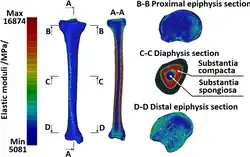

Lékařské záznamy rentgenového záření (CT) lze použít v biomechanice při tvorbě anatomických počítačových modelů lidských tkání vč. vyšetřování jejich struktury, hustoty a modulu pružnosti. Takto získané výsledky je možno použít také pro 3D tisk modelů orgánů či navržených implantátů. Podobné využití je také v paleontologii a archeologii při zkoumání struktury fosilií, mumií atp. Dalším cíleným zaměřením je také navigace lékařů při chirurgických úkonech (komplikované zlomeniny, vnitřní fixace, zevní fixace aj.).

- Příklad aplikace RTG záření v biomechanice[2]

Nehomogenní materiál, lidská tibie (zpracování CT snímků, separace kostní tkáně od měkkých tkání, tvorba CAD/MKP modelu v sw MIMICS a získané rozložení modulu pružnosti)

Nehomogenní materiál, lidská tibie (zpracování CT snímků, separace kostní tkáně od měkkých tkání, tvorba CAD/MKP modelu v sw MIMICS a získané rozložení modulu pružnosti) -

Nehomogenní materiál, lidská tibie (zpracování CT snímků, separace kostní tkáně od měkkých tkání, tvorba CAD/MKP modelu v sw MIMICS a získané rozložení modulu pružnosti)

Nehomogenní materiál, lidská tibie (zpracování CT snímků, separace kostní tkáně od měkkých tkání, tvorba CAD/MKP modelu v sw MIMICS a získané rozložení modulu pružnosti)